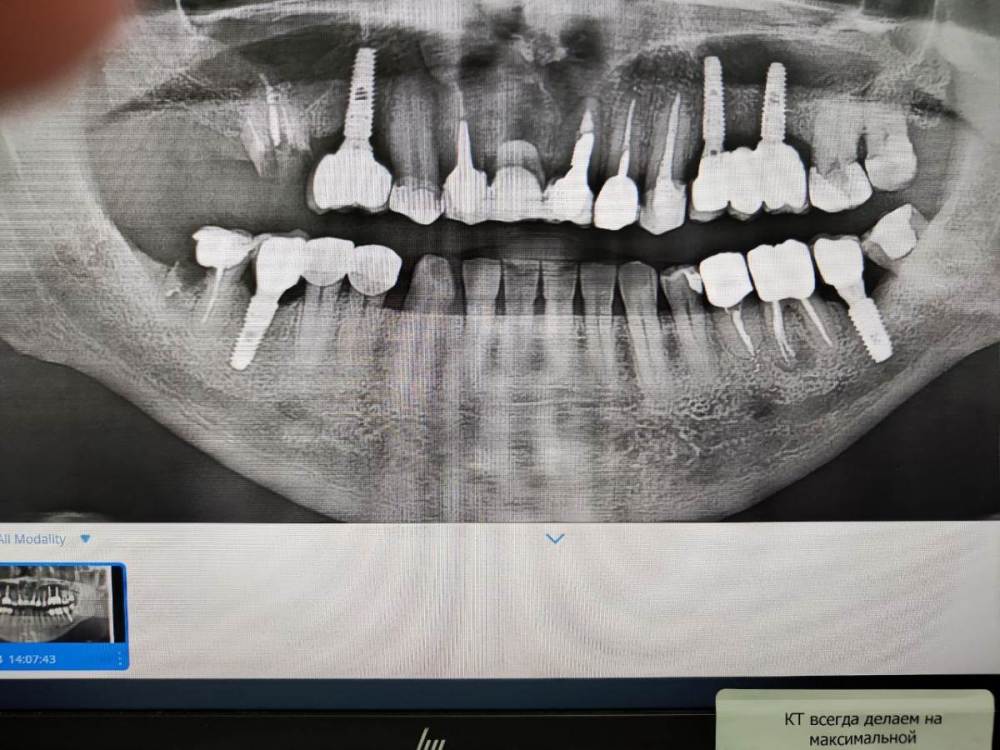

Мудрозуб Опубликовано 24 июля, 2023 Поделиться Опубликовано 24 июля, 2023 (изменено) 5 единиц в 2015 году. Импланты Ostem. Сейчас мне 55 лет. вот мое портфолио))). прикрепил снимок. Из проблем два раза в первые года слетала коронка с 37 зуба. На третий раз поставили на постоянный цемент. Стоит по сей день. Все остальные коронки на имплантах стоят на временном цементе. полгода назад раскрутился винт коронки на 15-ом зубе и коронка начала шататься, ортопед не смог сразу снять ее и я ходил так два дня. Потом все благополучно самооткрутилось и коронку я выловил в время трапезы. Отдали технику в работу и через пару дней поставили назад. Только совет если у вас произойдет такое надо бежать сразу к врачу чтобы отверстие в десне не заросло, а то потом больно будут делать )))))) Прошу оценить качество работы хирурга-имплантолога. Делали у доктора не из бюджетного сегмента , по рекомендациям знакомых. И еще наврное в следущий раз буду делать со сквозной винтовой фиксацией через коронку из диоксида циркония. Металлокерамика на мой взгляд с таким креплением как у меня это вчерашний день и проблемный вариант. Из проблемок Изменено 24 июля, 2023 пользователем Мудрозуб Ссылка на комментарий

Bier Опубликовано 4 октября, 2023 Поделиться Опубликовано 4 октября, 2023 хорошо все с имплантатами, а вот с зубами есть проблемки 1 Ссылка на комментарий

red_butler Опубликовано 5 октября, 2023 Поделиться Опубликовано 5 октября, 2023 Я бы сделал прицельные снимки имплантов на верхней челюсти... Ссылка на комментарий

Doc Опубликовано 7 октября, 2023 Поделиться Опубликовано 7 октября, 2023 Да, проблемы с зубами тут куда больше, чем с имплантатами. Ссылка на комментарий